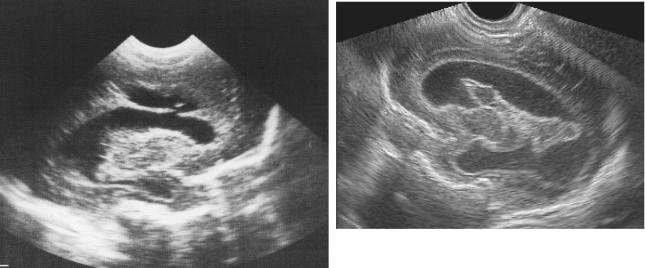

Динамика ПИВК представлена на рис. 6–11.

а

б

Рис. 6 (а). ПИВК I ст. Парасагиттальный срез. Гиперэхогенное образование округлой формы, небольших размеров в области каудо-таламической вырезки (субэпендимальное кровоизлияние).

Рис. 6 (б). Тот же ребенок. Коронарный срез. Субэпендимальное кровоизлияние справа.

Рис. 7. ПИВК III ст. Резкое расширение боковых и III желудочков мозга («острая» постгеморрагическая гидроцефалия). Сгустки крови в просвете боковых желудочков.